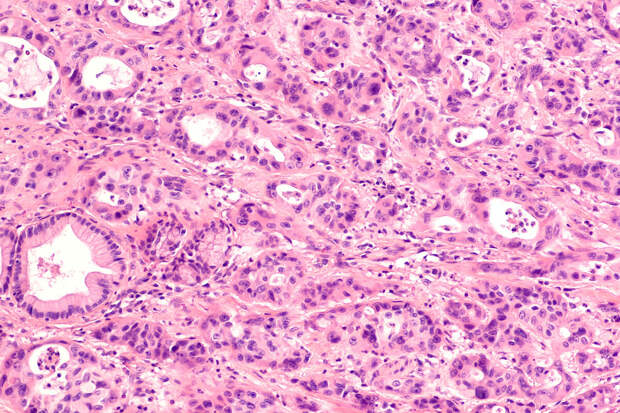

Согласно первому в мире рандомизированному исследованию, пациенты с запущенными формами рака желудка и желудочно-пищеводного соединения (ГЭП), получавшие эту терапию, жили в среднем на 40% дольше по сравнению с теми, кто проходил стандартное лечение.

CAR-T-терапия уже доказала свою эффективность против рака крови, но теперь ученые подтвердили ее потенциал в борьбе с солидными опухолями, которые составляют около 90% всех случаев рака, включая рак молочной железы, легких и поджелудочной железы.